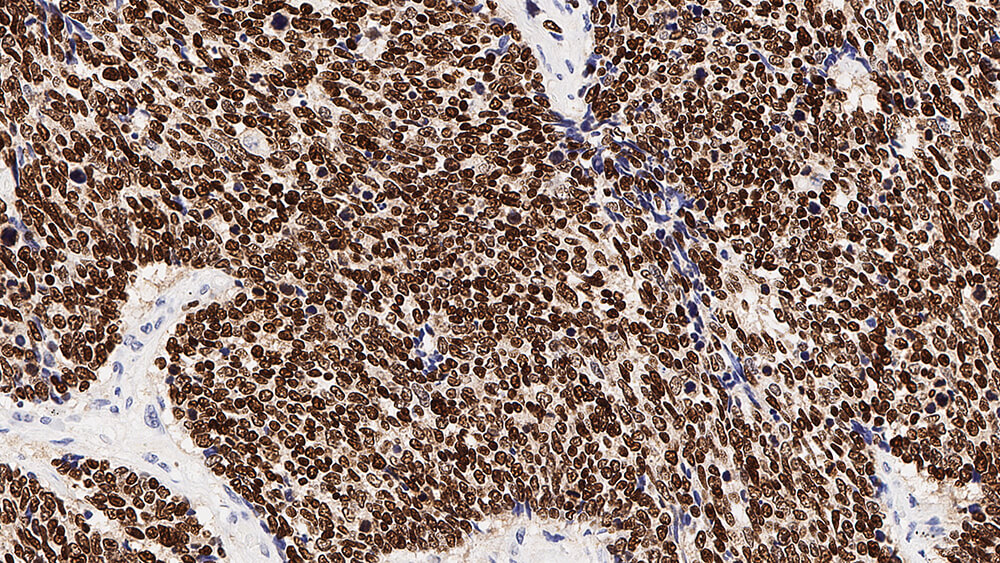

Human thyroid: immunohistochemical staining for Thyroid Transcription Factor-1. Note nuclear staining of thyroid epithelial cells. Thyroid Transcription Factor-1: clone SPT24

Le facteur 1 de transcription de la thyroïde (Thyroid Transcription Factor-1 ou TTF-1) est un membre de la famille des facteurs de transcription à homéodomaine, et joue un rôle dans la régulation des gènes exprimés dans la thyroïde, dans le poumon et dans le cerveau. Ceux-ci comprennent la thyroglobuline, la peroxydase thyroïdienne, la protéine sécrétoire des cellules de Clara et les protéines du surfactant.

L'expression du TTF-1 a été détectée dans plus de 90 pour cent des carcinomes pulmonaires à petites cellules et dans 75 pour cent des carcinomes pulmonaires non à petites cellules, mais il n'est pas exprimé dans les carcinoïdes pulmonaires typiques.

On a également observé l'expression du TTF-1 dans les carcinomes papillaires folliculaires et dans le goitre, un gonflement bénin de la thyroïde, mais pas dans les carcinomes anaplasiques de la thyroïde.